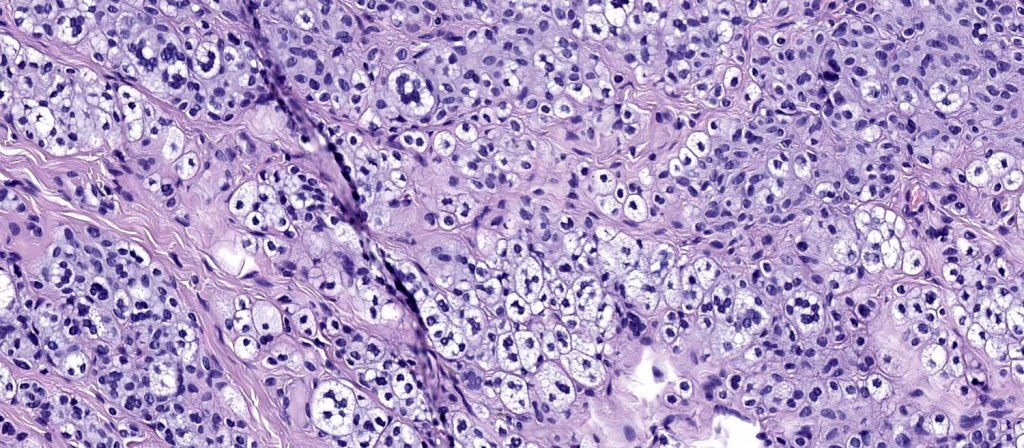

.Balloon cell change is most often seen in banal melanocytic nevi but it has also rarely been described in cellular blue nevus, dysplastic nevus, combined nevus, halo nevus & Spitz nevus. Lesions with <50% of balloon cells are sometimes described as nevi with balloon cells. Nevi with >50% balloon cells are described as balloon cell nevus.

.Balloon cell nevs genrally has uniform, hyperchromatic nuceli (as opposed to the vesicular nuclei with prominent nucleoli) seen in melanoma. Mitoses are absent.(In my experience, balloon cell melanoma is more common than balloon cell nevus).

. In some balloon cell nevi, the microvesicles may result in nuclear scalloping reminiscent of a sebaceous tumor. In cases where there is real doubt, immunohistochemistry (S100), SOX10) will resolve the problem.

The importance of the entity is that it must always be distinguished from balloon cell melanoma. All cases should be scrutinized very carefully for pleomorphism and mitotic activiy before rendering a diagnosis of balloon cell nevus.